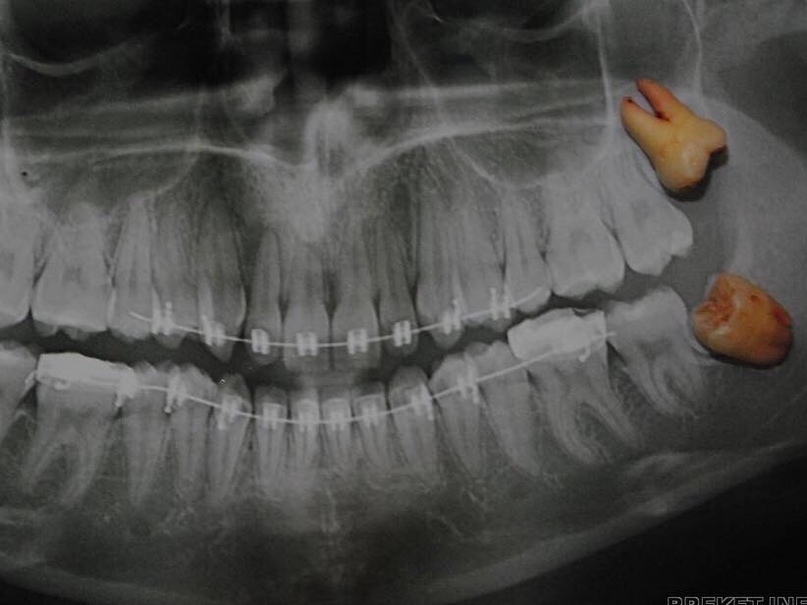

Дентальная галерея: ретинированный зуб клык и его лечение

Раздел: Компас решений